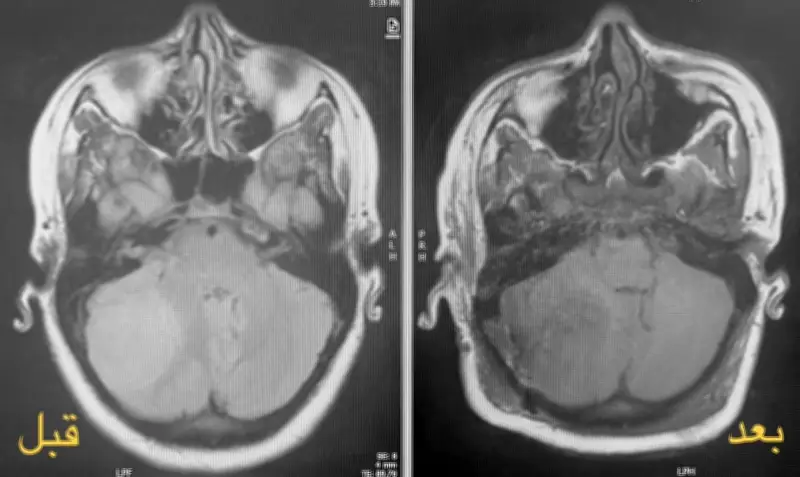

تطلبت الحالة الطبية تدخلاً جراحياً عاجلاً بسبب تشخيص ورم دماغي خطير لدى المريضة، التي كانت في مرحلة متقدمة من الحمل. شكلت العملية تحدياً كبيراً للفريق الطبي، حيث كان من الضروري إزالة الورم بالكامل مع ضمان عدم تعريض حياة الجنين لأي مخاطر.

استخدم الأطباء تقنيات جراحية متطورة وأجهزة مراقبة دقيقة خلال العملية، التي استمرت لعدة ساعات. تم التخطيط للعملية بعناية فائقة، مع مشاركة أخصائيين في جراحة الأعصاب والتخدير وطب النساء والتوليد، لضمان تحقيق أفضل النتائج.

أعلنت مدينة الملك سلمان الطبية أن العملية جرت بنجاح تام، حيث تم استئصال الورم الدماغي بالكامل دون أي مضاعفات. كما تم الحفاظ على سلامة الجنين طوال فترة التدخل الجراحي، مما يعكس الكفاءة العالية للفريق الطبي والبنية التحتية المتطورة للمستشفى.